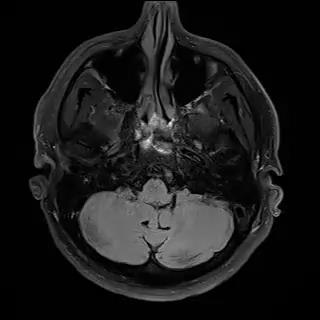

- Abnormality detection, acute infarction, acute hemorrhage, mass effect

Sagittal T1W, FLAIR, TraceW, & ADC

Processing mpMRI data after repositioning via landmarks & skull stripping

AI system

Trained on 25,000 MRI studies